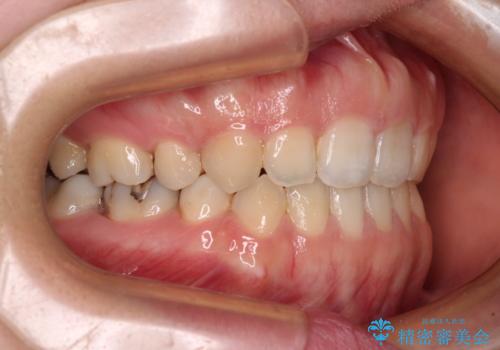

- 矯正装置

- 審美装置

- 口元の膨らみが気になるとのことで来院された患者様です。

非抜歯で口元の突出感を少し改善させる治療も提案しましたが、最大限口元を引っ込めたいとのことでした。

上下左右第一小臼歯4本を抜歯し、ワイヤー装置により矯正治療を行うこととしました。

治療は順調に進み、予定された期間で終了することができました。

装置除去後には、スッキリとした口元となり、大変満足していただきました。